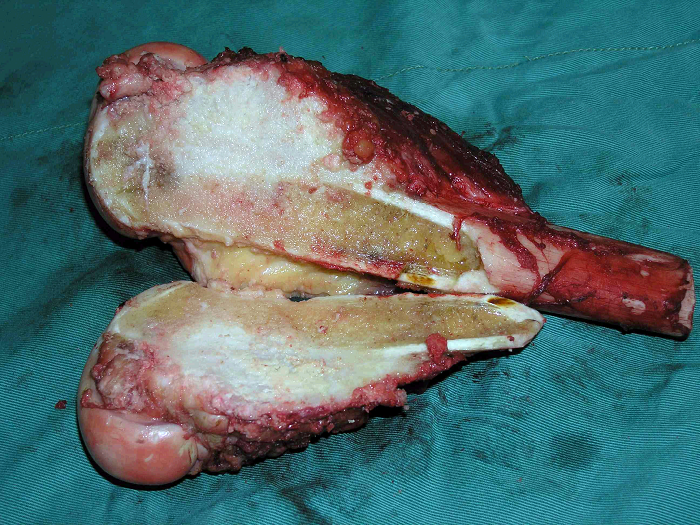

5、病例5:男 65岁 左胫骨上段毛细血管扩张性骨肉瘤,因活检术后持续性出血,行大腿中段截肢术

图 31 肿瘤病灶外观

图 32 组织学特点:在扩张的血管间

见异型成骨细胞,正常的骨小梁

被破坏。